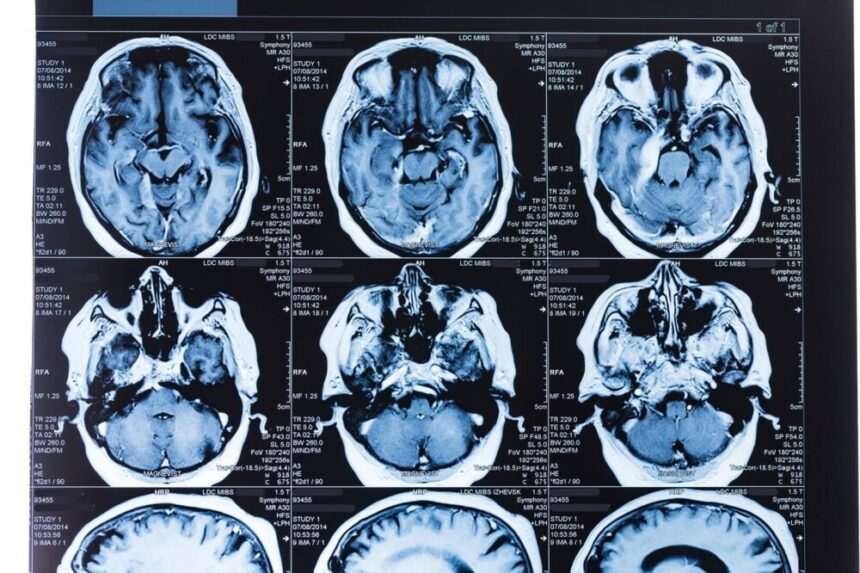

Potrivit datelor publicate în jurnalul Neurology, cei care fac munci care presupun multă rutină prezintă risc mai mare, de până la 66 de procente, să dezvolte tulburări cognitive la bătrânețe, iar riscul de a face demență după 70 de ani crește cu 37%. E vorba în special de muncitorii din fabrici, depozite sau magazine, ori de bibliotecari, persoane care au o activitatea manuală repetitivă, arată concluziile studiului.

Cei care au profesii care le pun creierul la încercare – medicii, avocații, contabilii, ori inginerii – au un risc mai mic de a dezvolta insuficiență cognitivă la pensie. Au slujbe care presupun gândire complexă și creativă. În plus, arată studiul, și interacțiunile de la serviciu ne ajută să ne păstrăm creierul tânăr mai mult timp.

În momentul de față, nu există niciun tratament care vindecă demența. Medicii prescriu, însă, medicamente și terapii care încetinesc evoluția bolii.